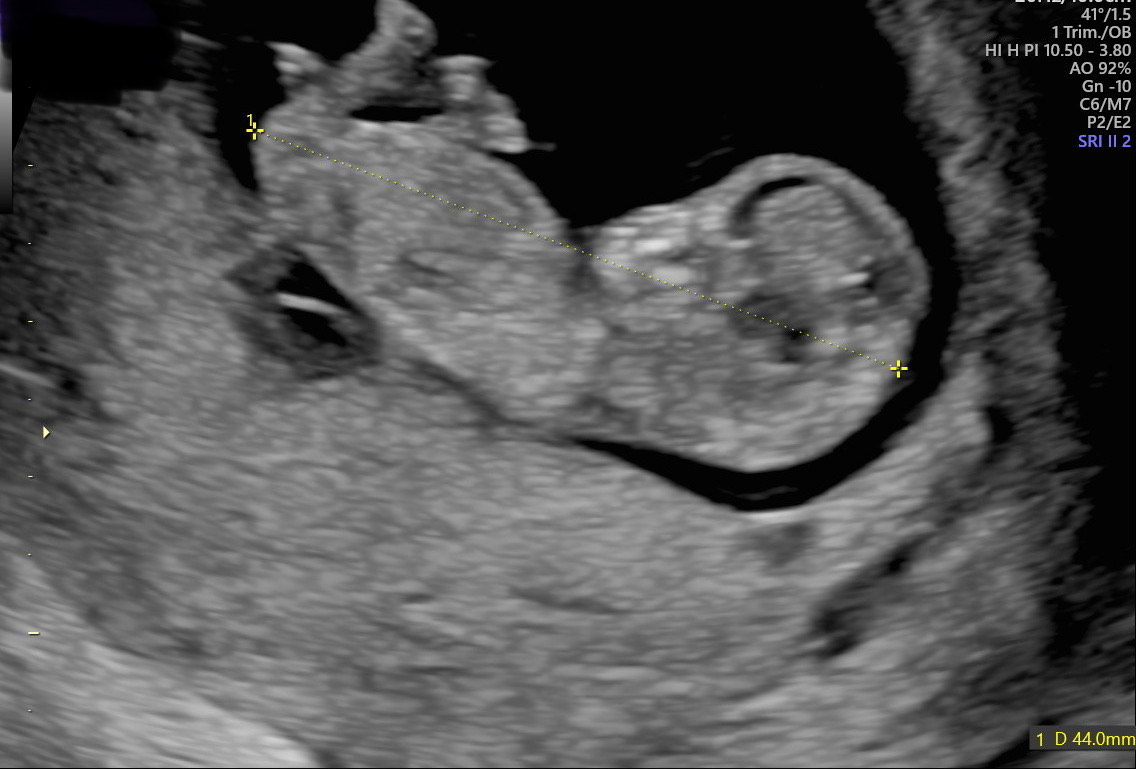

Just had my ultrasound and I am currently 11w and 2 days pregnant. I have some pictures of the scan... Think I see a boy nub at some pics? Some also are a little girlish (flat) too? Of course I am not a doctor so I am not really sure what we are looking at exactly haha...

Added a few pictures, because I think they are all a little different... Also because the baby is laying a little tilted..

Is this too early to see the nub or is this already early enough to predict gender?